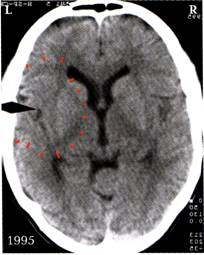

2. ábra: A bal oldalon látható nyíl ugyanarra az exhibicionista által okozott „szexuális konfliktus”-ra utal. Látható a góc körüli a halvány ödémperem. Mivel a páciens a birtokbosszankodást / eséskonfliktust időközben már megoldotta, feloldhatóvá válhat végre a bal féltekei Hameri góc, mely ugye másodikként csapódott be. Úgy tűnik azonban, hogy ezen még nem tudta magát túltenni, mert jelenleg a nigériai barátjával nézeteltérései vannak, melyek ezen a sínen futnak. Így a „szexuális konfliktus”-a soha nem kerül igazán feloldásra.